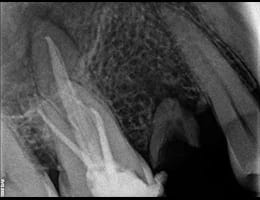

The dentist examines the tooth and takes X-rays to confirm the extent of infection or damage.

The infected or damaged pulp is removed using specialized instruments. The root canals are then cleaned and shaped to ensure they are free of bacteria and debris.

The cleaned canals are filled with a biocompatible material, usually gutta-percha, to seal them and prevent future infection.

DIGITAL X RAY “RVG”

We invest in the latest imaging technologies like Carestream RVG IOPA to provide superior diagnostic capabilities.